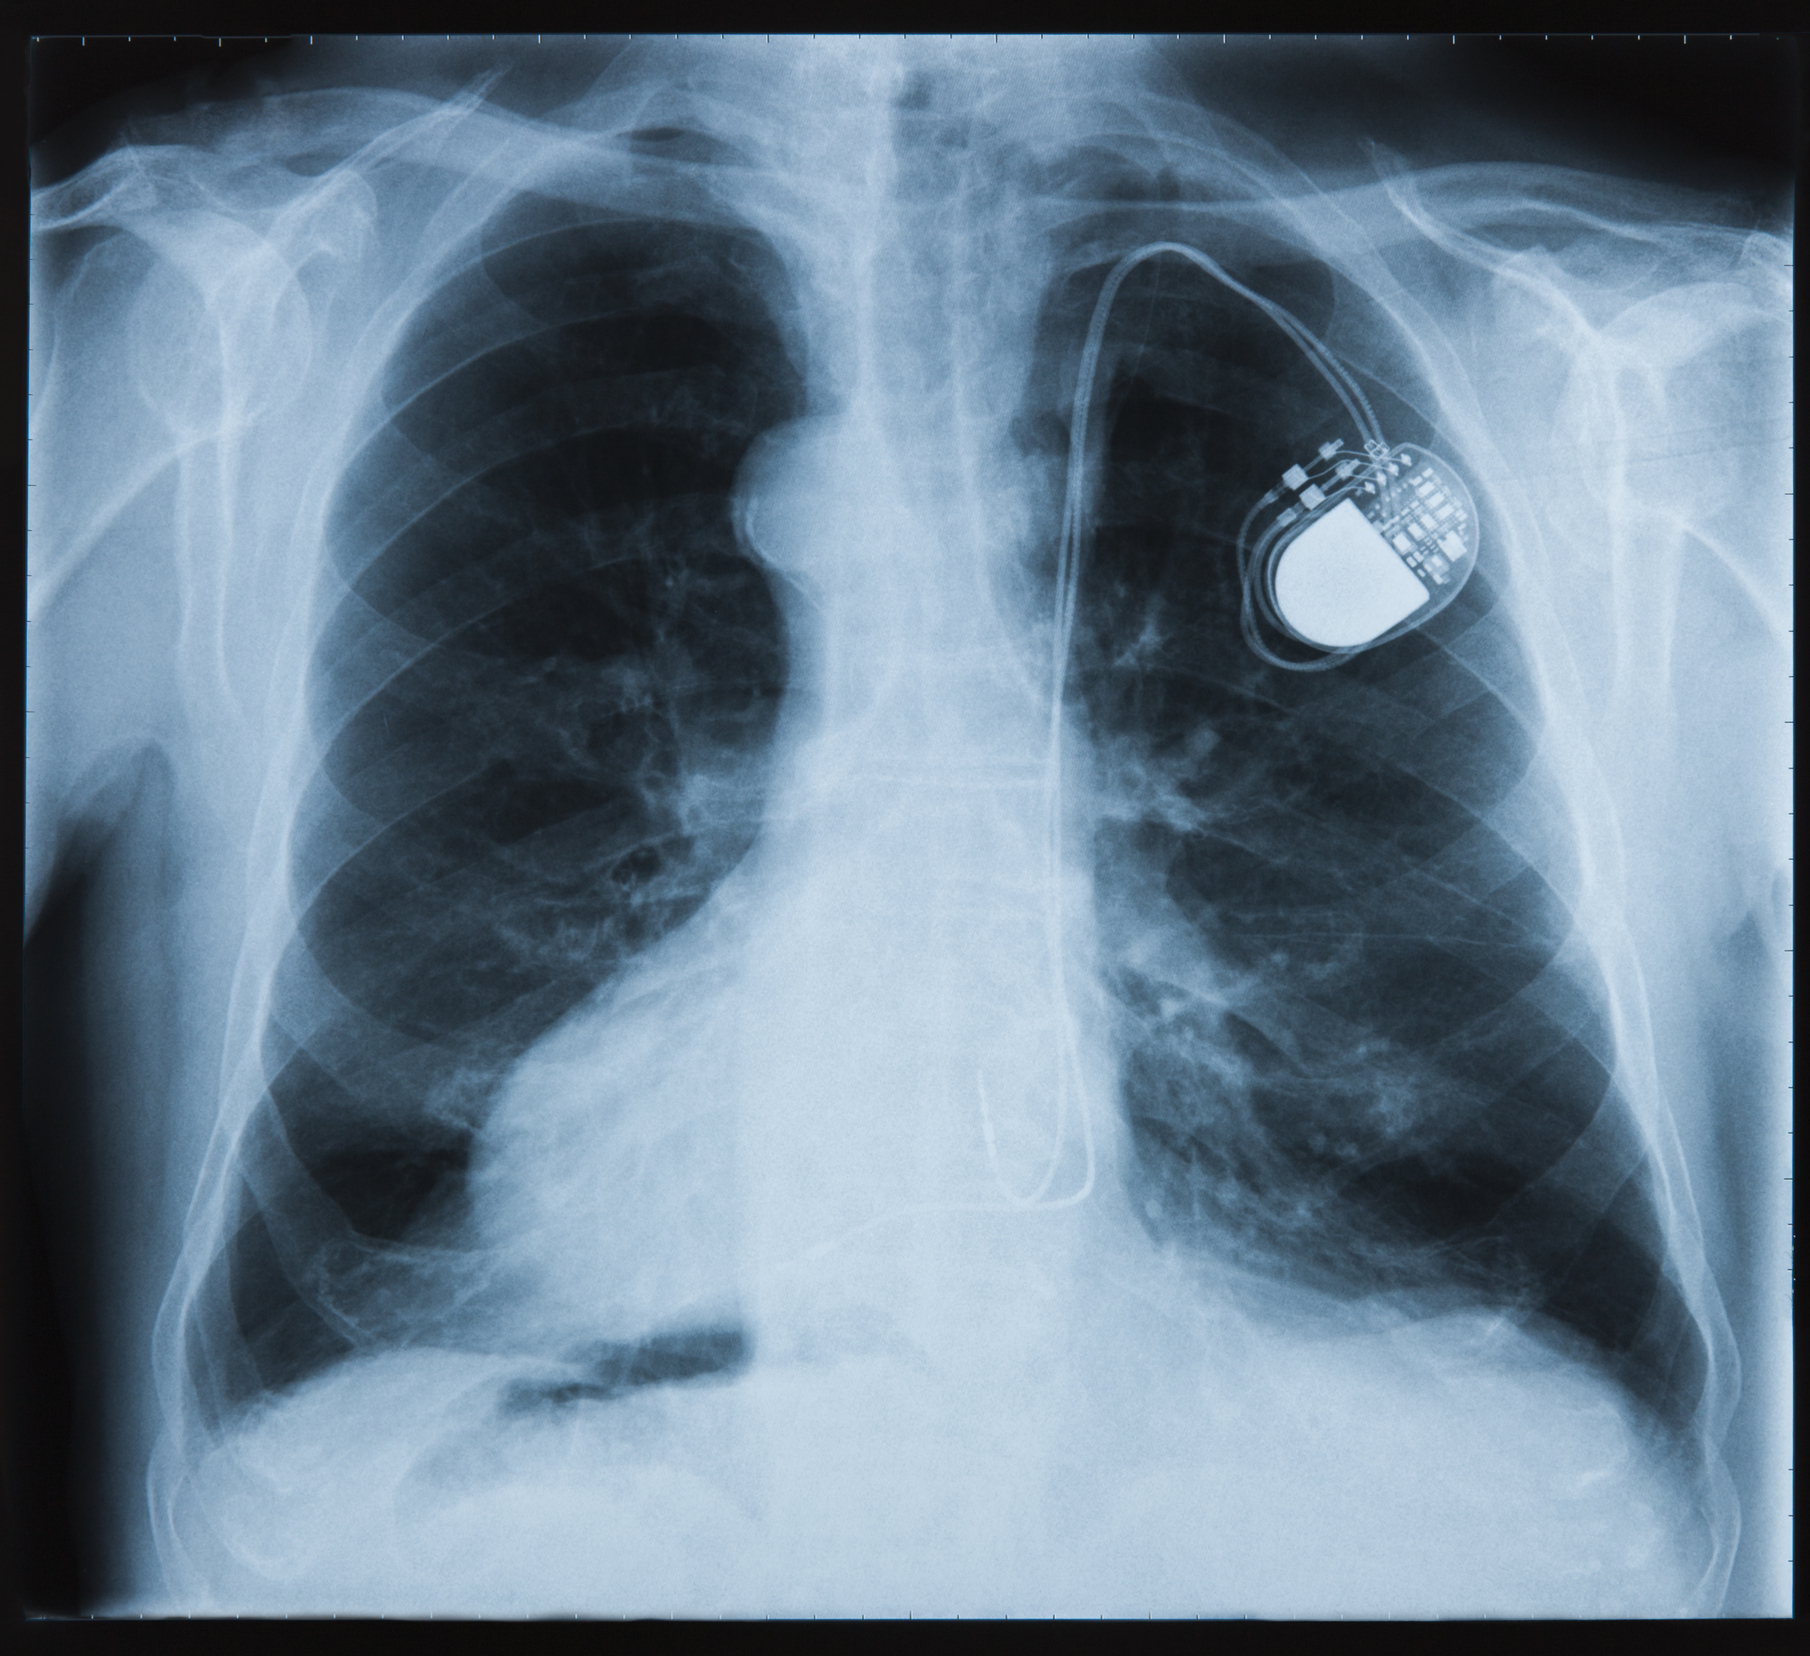

Oslo universitetssykehus har innført nye rutiner for undersøkelser i magnetisk resonans (MR) av pasienter med pacemaker eller implanterbar defibrillator (implantable cardioverter-defibrillator, ICD). Vi har prosedyre for både MR-tilpasset og ikke-MR-tilpasset utstyr. Innstillingene til pacemaker og implanterbar defibrillator må endres av pacemakerkyndig personell før og etter MR-undersøkelse. Individuell, tverrfaglig risikovurdering er nødvendig for ikke-MR-tilpassede enheter.

Stadig flere får pacemaker eller implanterbar defibrillator, noe de som regel vil ha livet ut. Implantatene har vært regnet som absolutt kontraindikasjon mot magnetisk resonanstomografi (MR-undersøkelse). Likevel vil mange trenge MR-undersøkelse i løpet av livet. En studie estimerte at over halvparten av alle med slike anlegg vil få behov for MR-undersøkelse i løpet av ti år (1). Å utelate nødvendige MR-undersøkelser kan også innebære medisinsk risiko.